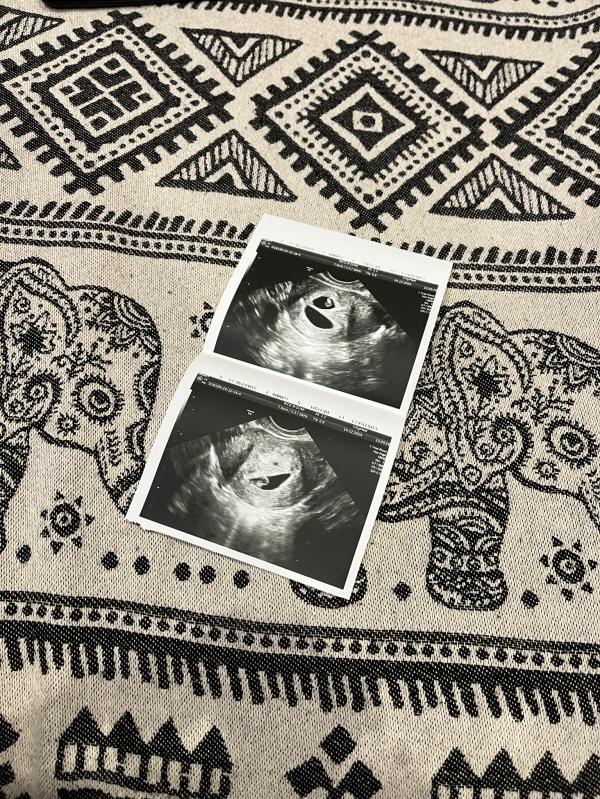

Пошла на узи, рано, пока ещё ничего не видно. Врач сказал придти через пару дней. Я пришла в назначенный день, она вводит датчик и говорит: «Двойня».

Дихориальная диамниотическая двойня.

Еле дождалась окончания рабочего дня, муж встретил с работы, я дала ему фото узи. Он говорит: и что?

Я: - Сколько точек ты тут видишь?

Последнее фото самое интересное, лежат как в плацкарте😄🥹😍